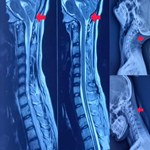

Type I Arnold Chiari malformation with an accompanying bifid spinous process at the C3 vertebra in a 19-year-old female

Aditi Pradip Ambekar, Sharath Hullumani

PAMJ-CM. 2025; 17: 18. Published 18 February 2025